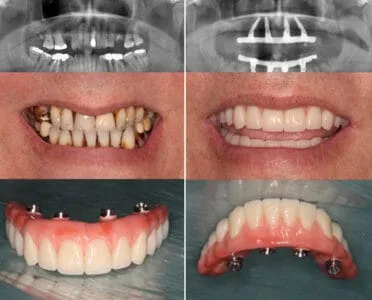

Digital Dental Implants Before and After (Photo Results)

Digital dental implant treatment often produces highly predictable and aesthetically pleasing results. Before-and-after images typically show:– Replacement of missing teeth with natural-looking restorations – Improved smile line, tooth shape, and alignment – Restoration of facial support in areas of bone lossYour dentist can show you actual case photos that match your situation to help you understand the expected outcome.